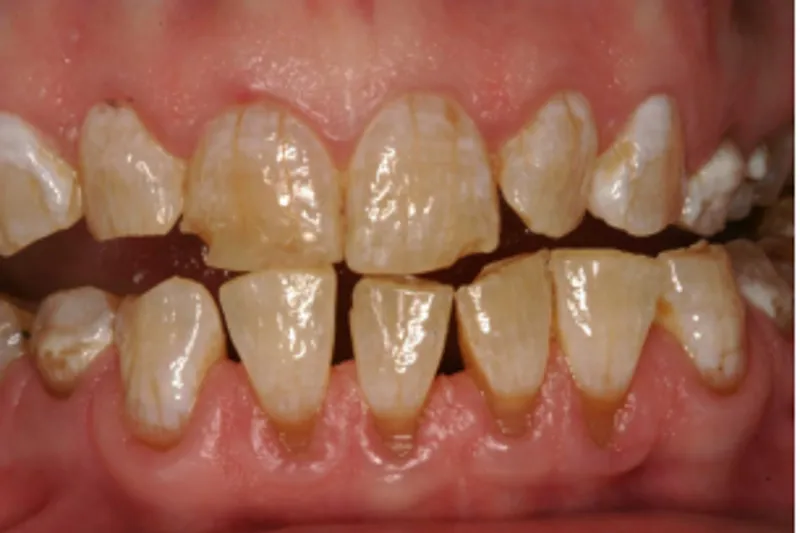

Patienter med amelogenesis imperfecta (AI) har oftest et livslangt behandlingsbehov, fordi insufficient mineraliseret emalje fører til fraktur, slid, symptomer, caries, begrænset holdbarhed af restaureringer og insufficient æstetik. Det er derfor vigtigt, at behandlingsvalg relateres til patientens alder og behov, samt at en noninvasiv tilgang tilstræbes.

I denne artikel gennemgås behandlingen af en 42-årig kvinde med amelogenesis imperfecta, hvor slid og insufficient æstetik længe har været et problem. Der udføres bidhævning med en kombination af direkte plast og keramiske restaureringer og noninvasiv æstetisk behandling i fronten med keramiske skalkroner og direkte plast. De kliniske procedurer beskrives udførligt undervejs. Til sidst diskuteres forskellige behandlingsmuligheder for AI-patienter og for patienter med behov for rekonstruktion af biddet.